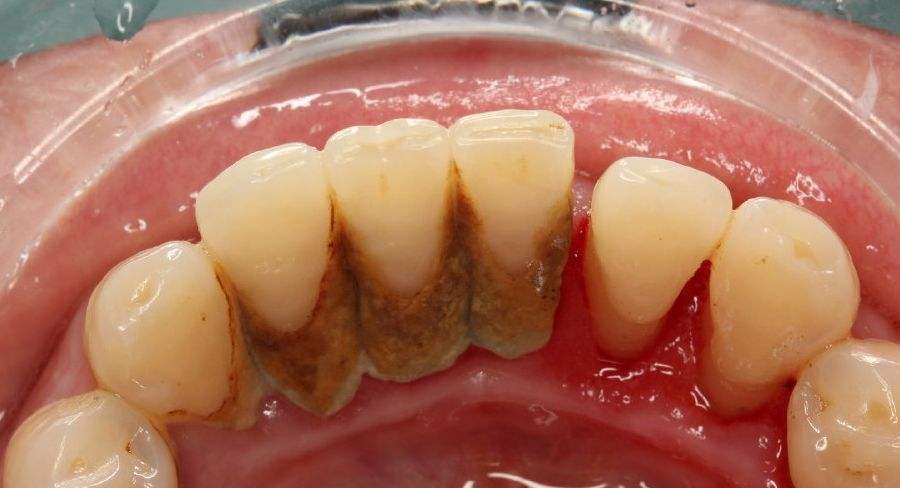

牙结石也是我们通常讲的牙石,主要成分是磷酸钙,一般是在下侧牙齿内侧积累呈现,我们可以观察到的是乳白色的软垢,随着时间推移会逐渐钙化,继而颜色变深,结石也会变硬,继而导致更为严重的牙周问题。

牙结石一旦成型,是很难通过刷牙来清除掉的,不仅会逐渐增多,甚至会越来越硬,形成肉眼可见的牙结石。